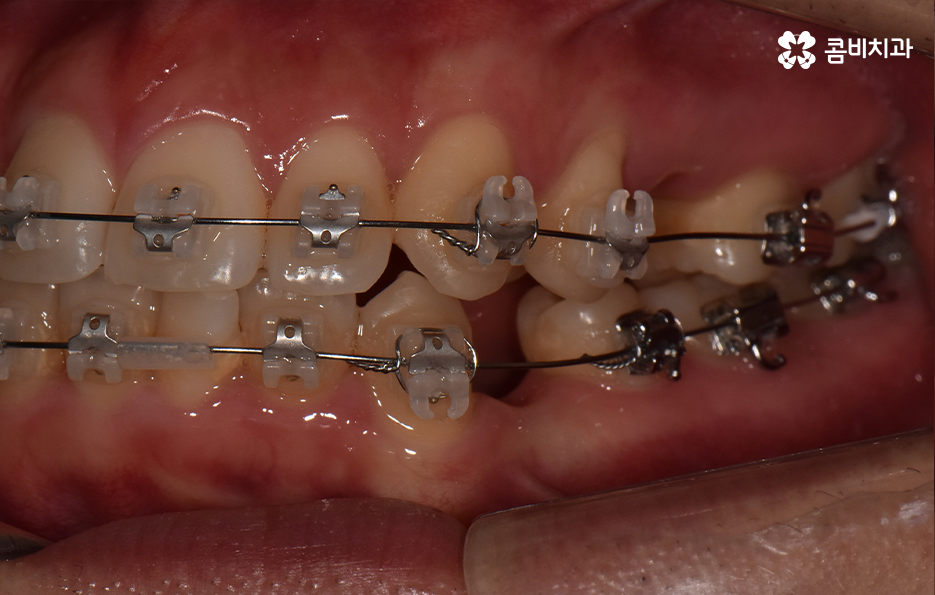

덧니가 나는 원인은 유전적인 영향부터 골격적인 부분 등 다양하지만 기본적으로는 치아가 나올 공간이 부족해서 덧니의 형태로 영구치가 자라는 경우가 많기 때문에 덧니 교정 사례에는 유독 발치 교정 사례가 많이 있는데요

요즘은 앞니만 약간 벌어져도 교정을 하는 분들이 크게 늘고 있기 때문에 덧니가 심하지 않아도 교정을 하는 분들도 많기 때문에 덧니 교정 사례에서도 비발치 사례도 많지만 보편적으로 덧니 발치교정 사례가 많은 것도 사실이기 때문에 어떠한 경우에는 발치교정이 필요하며 또한 어떻게 치아교정 계획을 세우는 것이 좋을지 오늘 포스팅에서 알아볼 거예요

다만 덧니 교정 사례에서 발치교정 사례가 많은 이유는 턱뼈가 좁아서 치아가 덧니로 자란 경우가 많기 때문에 치열을 재배열하기 위해서는 치아가 움직일 수 있는 충분한 이동공간이 필요하기 때문에 공간 확보의 목적으로서 작은 어금니 양옆, 위아래 4개를 발치를 하는 발치교정법이 보편적으로 많이 활용되고 있으며 치아의 이동 공간을 확보하는 방법으로는 발치 교정법 외에도 악궁확장, 어금니 후방이동, 치간삭제와 같은 비발치적인 방법도 가능하기 때문에 치아를 얼마나 이동시켜야 할지에 따라서 치료법은 개인차가 발생되고 있어요